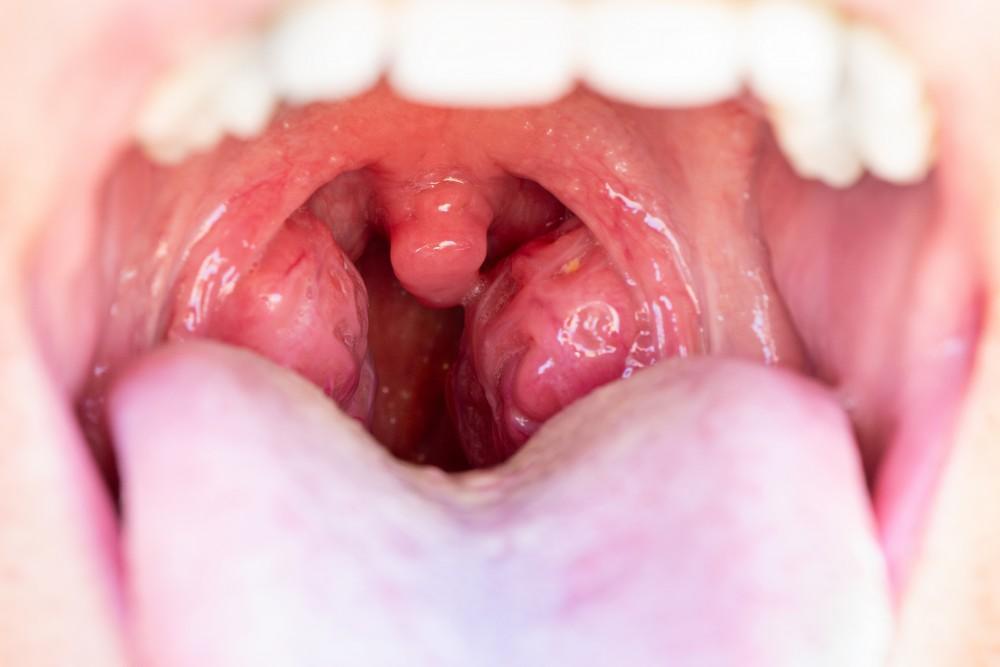

Upala krajnika, poznata i kao tonzilitis, nastaje kada krajnike zahvate virusi ili bakterije. Tada govorimo o upaljenim krajnicima kod dece, što je drugačije stanje od pukog uvećanja.

Najčešći simptomi upale krajnika su:

- bol u grlu

- otežano gutanje

- crveni i otečeni krajnici

- povišena temperatura (ali ne uvek)

- uvećani limfni čvorovi na vratu.

Razlika između uvećanih, otečenih i upaljenih krajnika kod dece nije u njihovoj veličini, već u ponašanju deteta. Krajnici koji su stalno veći, ali ne menjaju boju, ne bole i ne utiču na ishranu ili raspoloženje, obično su samo uvećani.

Kada se krajnici naglo promene — postanu osetljivi, dete počne da izbegava gutanje, postane klonulo ili se javi bol — tada uvećanje prelazi u oticanje i upalu.

3. Koja je razlika između uvećanih i upaljenih krajnika?

Upaljeni krajnici kod dece (tonzilitis) podrazumevaju infekciju – najčešće virusnu ili bakterijsku. Tada su prisutni simptomi poput bola u grlu, povišene temperature, otežanog gutanja i malaksalosti.

Sa druge strane, uvecani krajnici ne moraju biti upaljeni – mogu biti povećani i bez znakova infekcije. Ključna razlika je prisustvo simptoma upale.